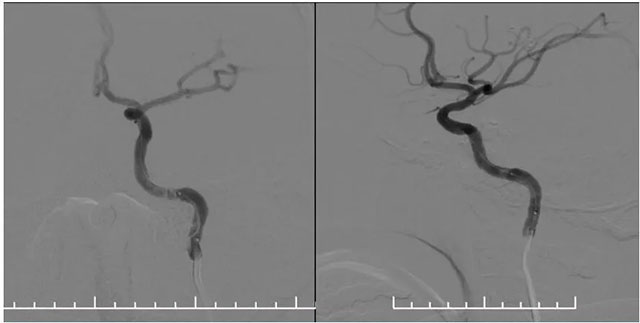

▲ 药物洗脱球囊在微导丝导引下到位于左侧椎动脉支架内,充分扩张药物球囊使其贴壁

再次超选至左侧锁骨下动脉近椎动脉开口处,单次造影后明确开口狭窄程度,测量狭窄段长度及近远端血管直径,选取合适球囊。随后在微导丝辅助下通过支架内再狭窄段超选至左侧椎动脉V2段,选用2.5*15球囊,沿微导丝到位于狭窄段,球囊扩张至8atm,再次行椎动脉造影,血流有所改善。再次将球囊下移,球囊扩张至14atm,撤除球囊后行即刻造影示血流较前通畅。选择3.5*15药物洗脱球囊,超选至狭窄处,予以6atm,后撤除球囊,行即刻造影示血流较前明显改善,再次行椎动脉造影双侧大脑后动脉及基底动脉血流通畅。

▲ 球囊扩张后,支架内狭窄明显改善,支架贴壁良好